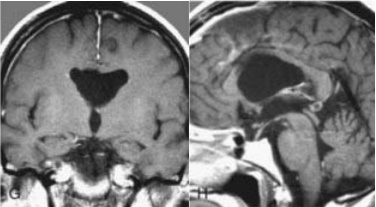

术后MRI

术中证实为一实质性、血供丰富的室管膜下瘤,经显微手术完全切除,术后MRI证实肿瘤全切,患者术后无神经功能障碍及其他并发症。